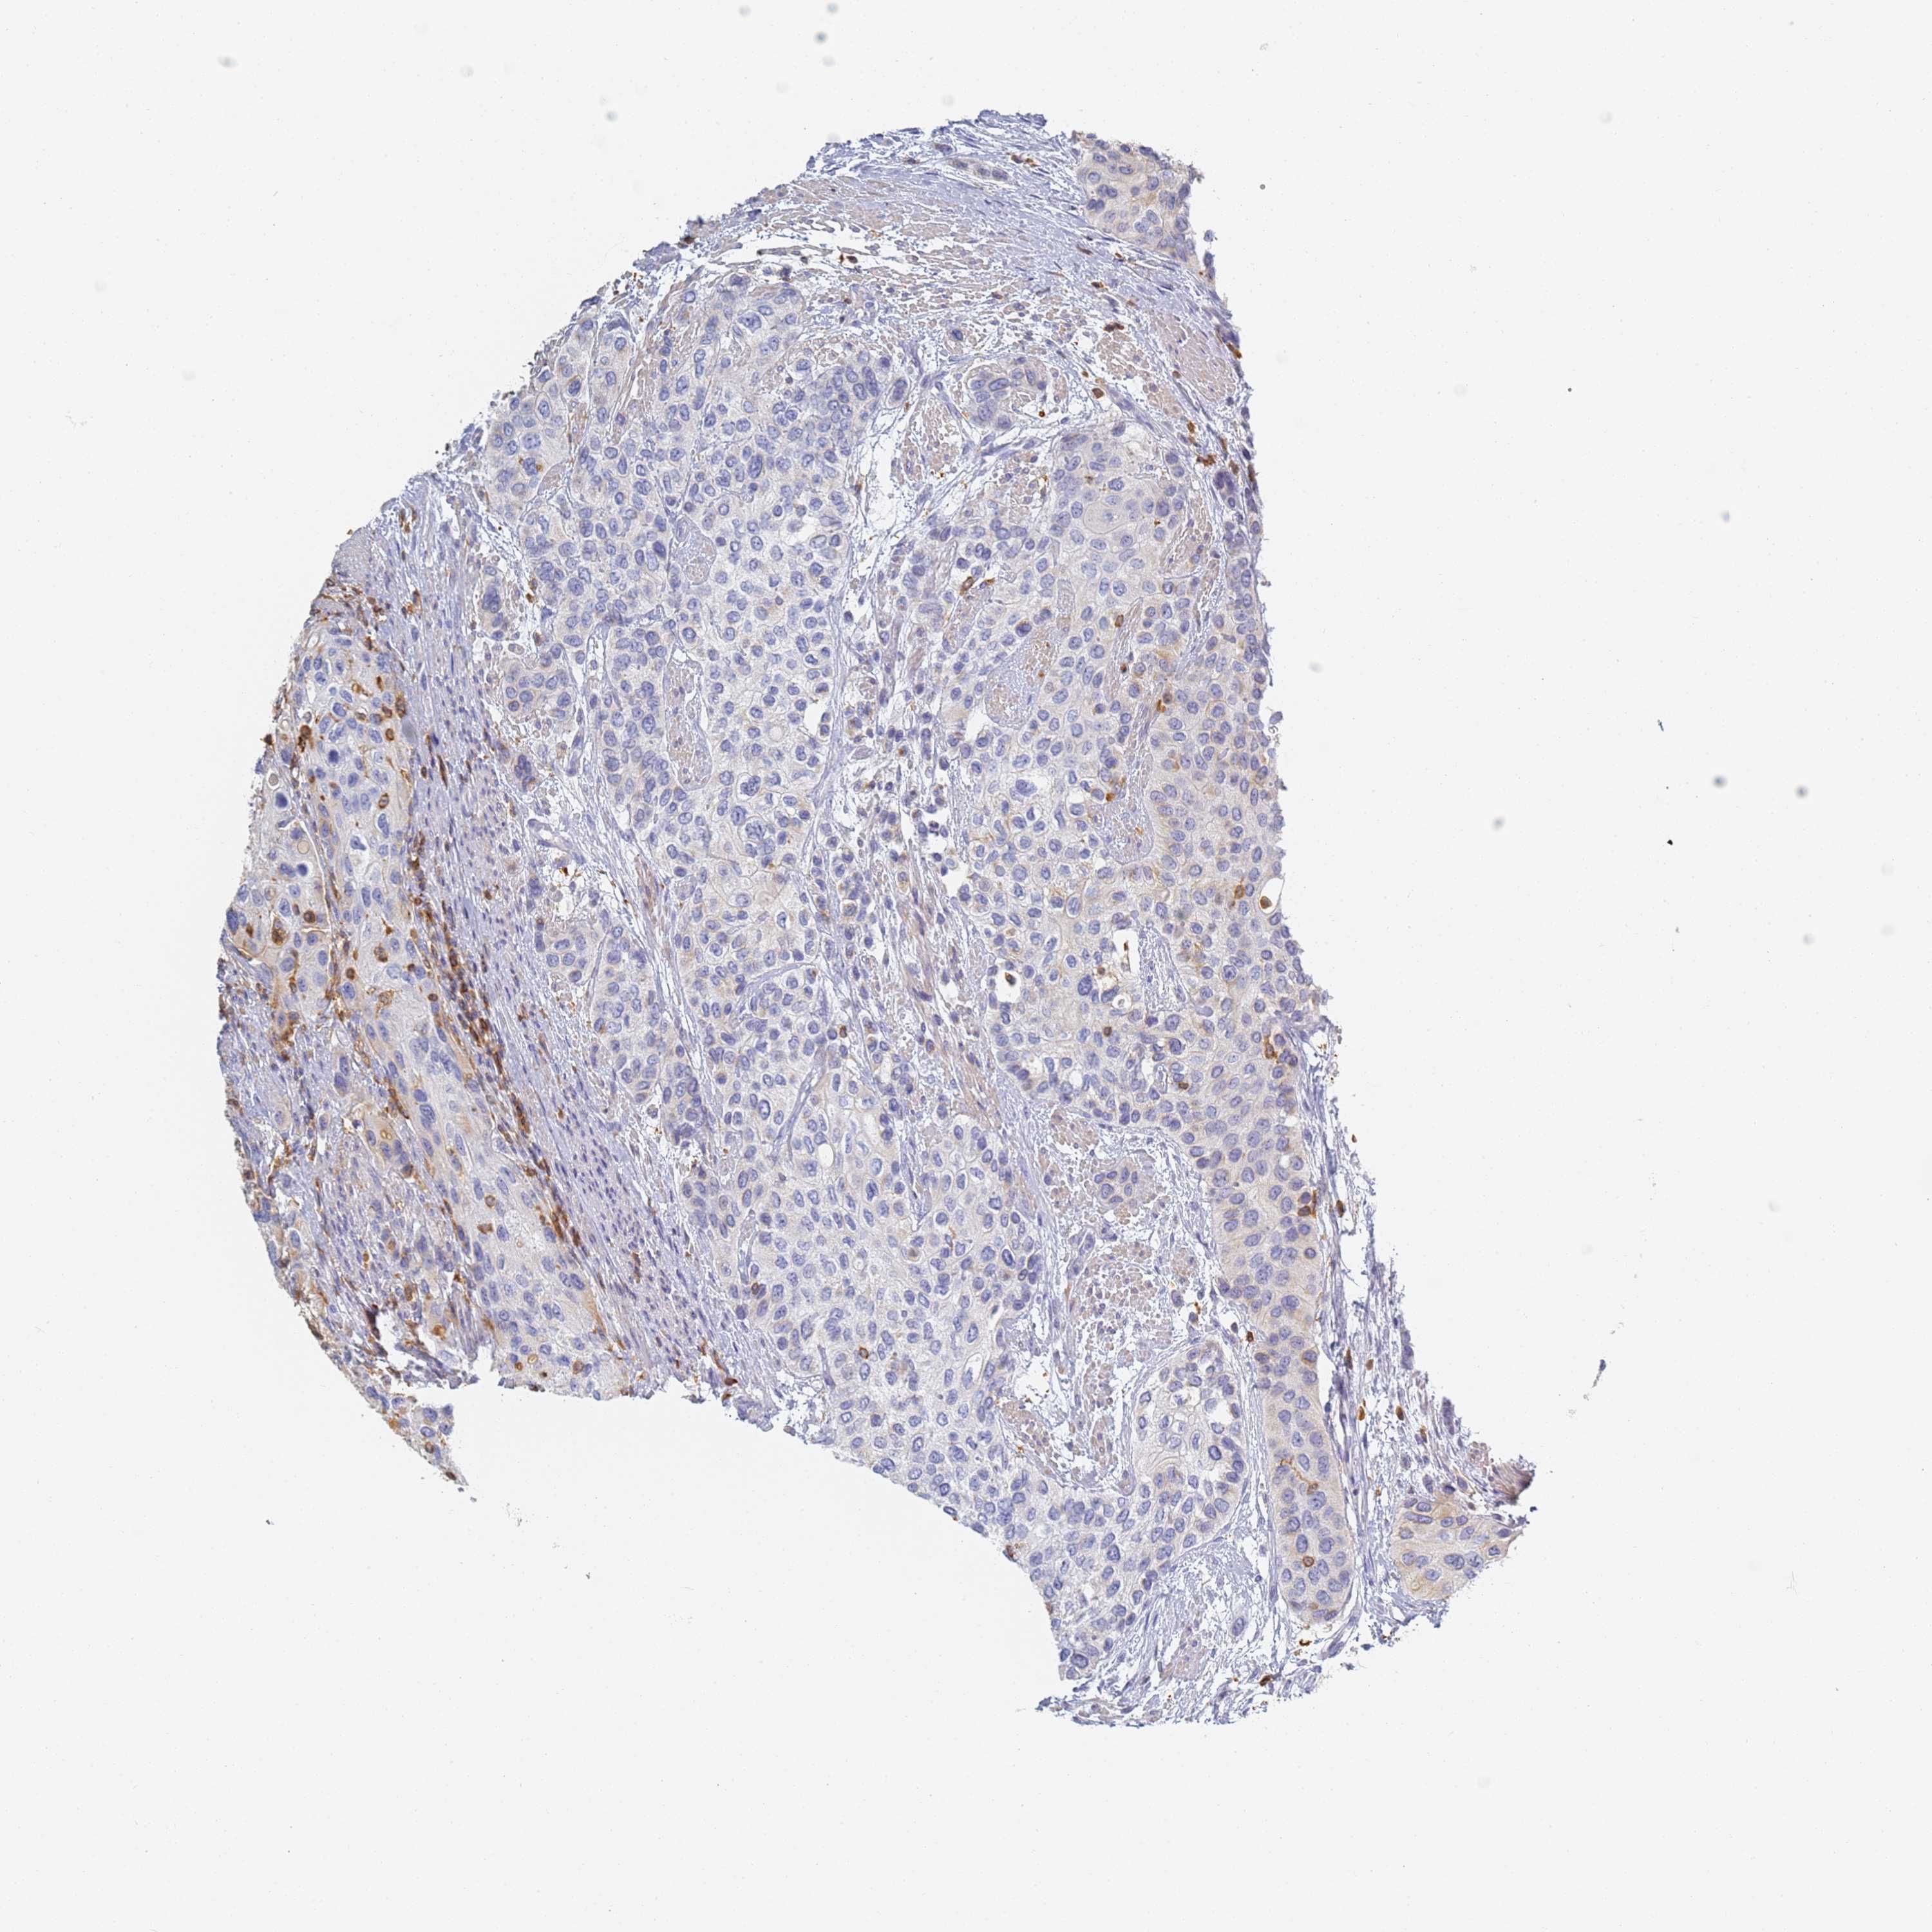

UROTHELIAL CANCER - Protein expressioni

A mouse-over function shows sample information and annotation data. Click on an image to view it in a full screen mode. Samples can be filtered based on level of antibody staining by selecting one or several of the following categories: high, medium, low and not detected. The assay and annotation is described here.

Antibody stainingi

Antibody staining in the annotated cell types in the current human tissue is reported as not detected, low, medium, or high, based on conventional immunohistochemistry profiling in selected tissues. This score is based on the combination of the staining intensity and fraction of stained cells.

Each image is clickable and will lead to virtual microscopy that enables deeper exploration of all samples and also displays staining intensity scores, fraction scores and subcellular localization as well as patient and tissue information for each sample.

Antibody HPA038666

Antibody HPA038667

Urothelial carcinoma, High grade

Urothelial carcinoma, Low grade